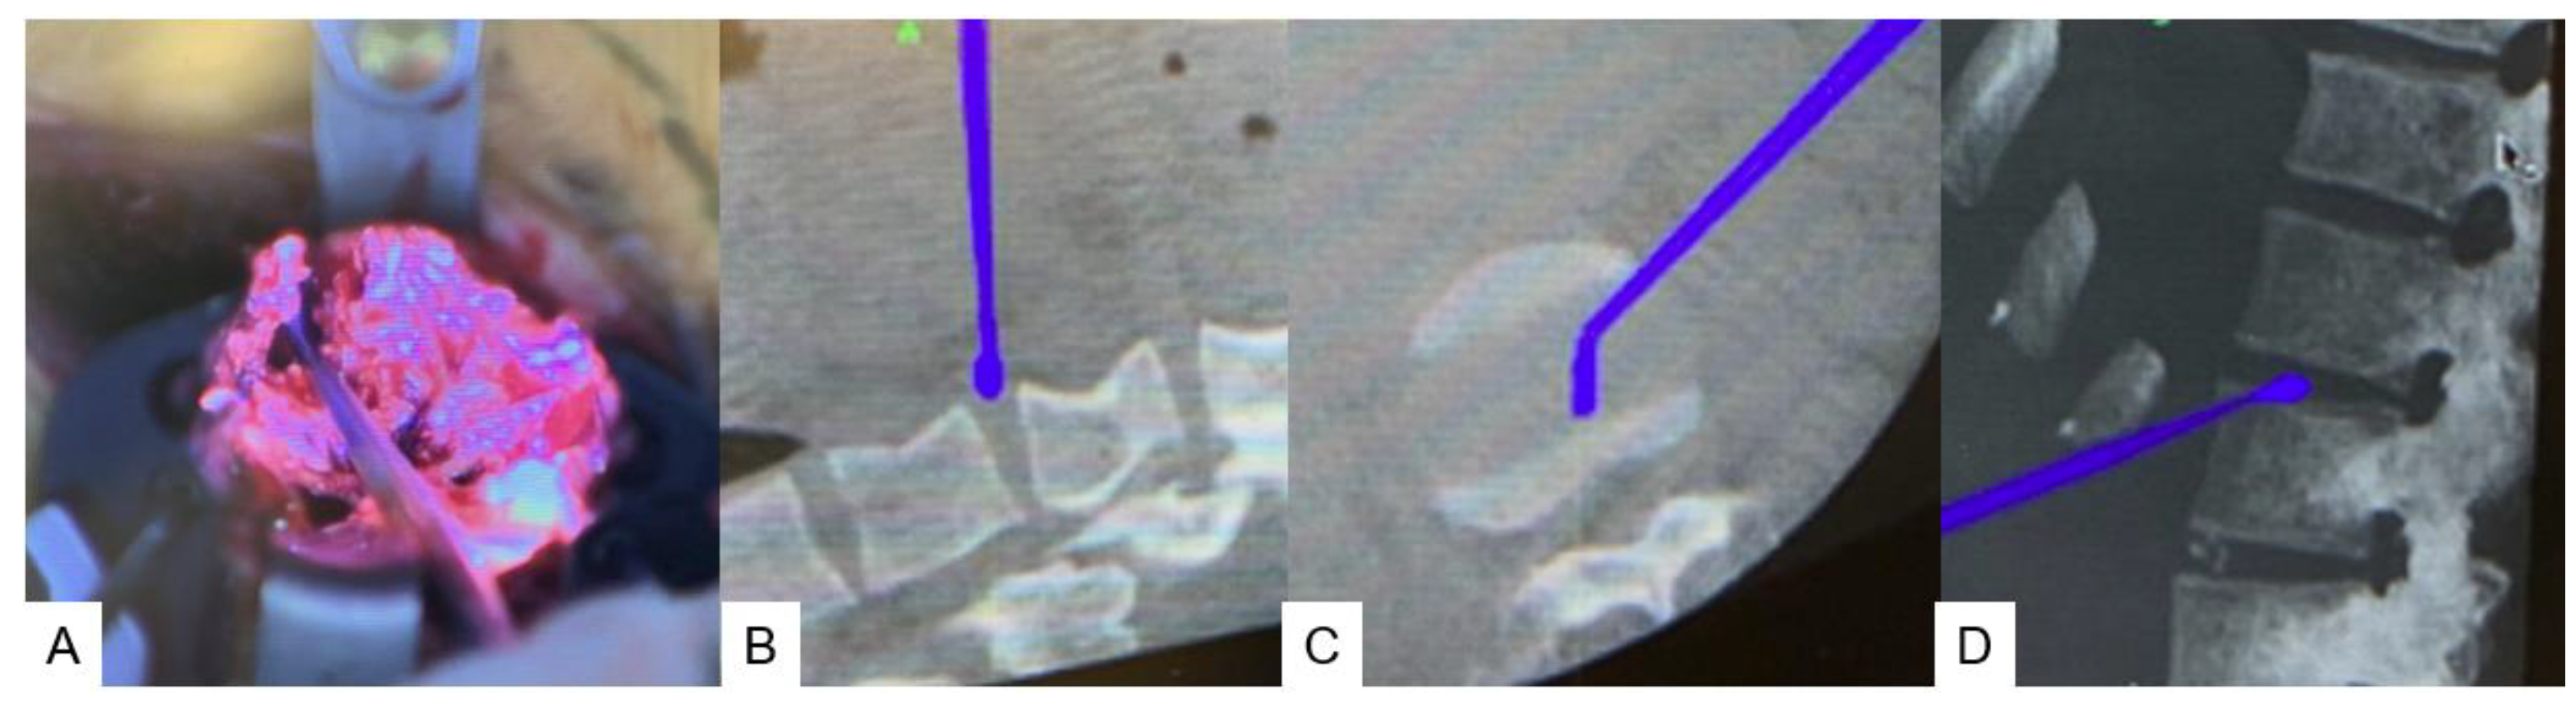

2.4. Surgery

2.4.1. Anterior disectomy

2.4.2. Posterior osteotomy